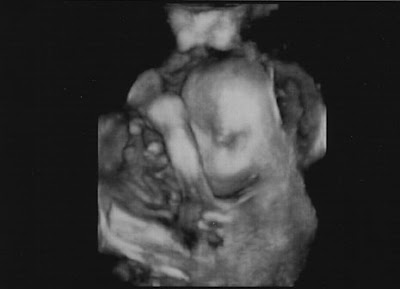

Finally the sonographer backed off and we were able to see some face.

This was the best image. As an added bonus it looks like the baby may look more like me than my husband. Oh boy, but that is a different story. It is funny when both of your parents are so different looking. My husband and I have been super curious what this baby would look like.